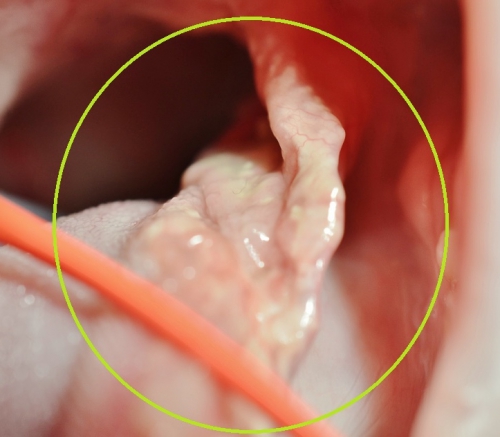

胃内での異物の状態が不明なため、手術と同時に口から内視鏡を使って胃内を検査しているところが上の写真です。

その結果、なんと内視鏡検査で新たに「3匹目」と「4匹目」のネズミが胃の中に留まっていることが判明いたしました。

胃の中の3匹目と十二指腸の2匹目をつなげているヒモ状物を切断した後、内視鏡で「3匹目のネズミ」と「4匹目のネズミ」を摘出いたしました。